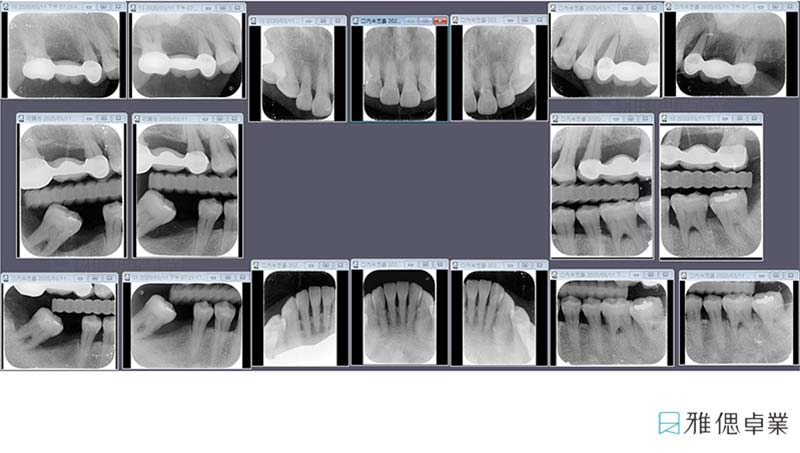

① 確認牙周病病程及治療方向,初診檢查:全口X光檢查,全口牙周檢查,全口牙齒相關問題檢查。

② 根尖X光片18張,記錄齒槽骨被破壞的程度